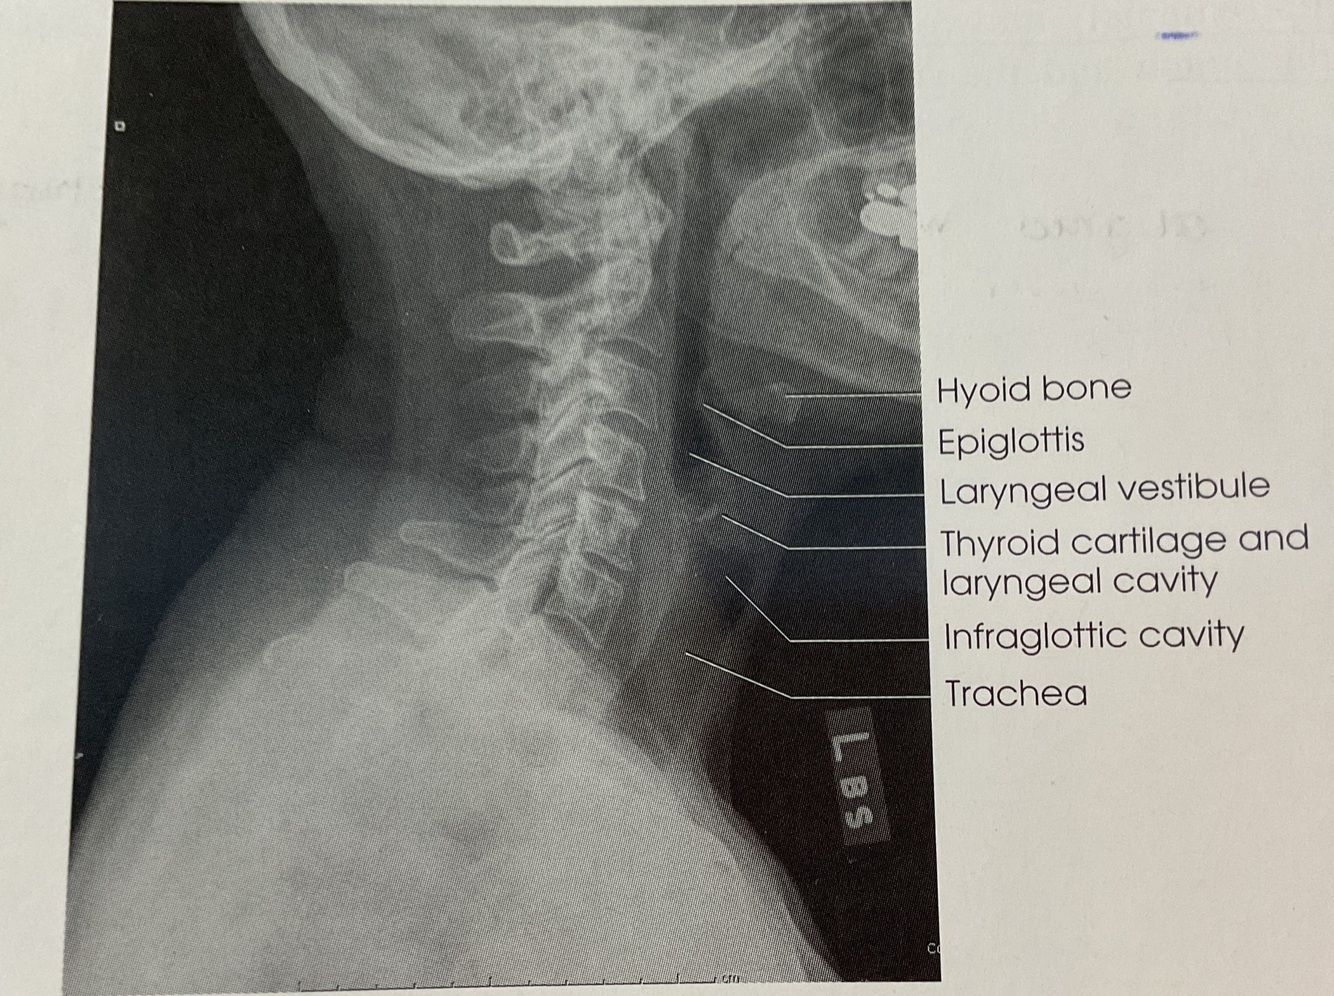

Soft tissue neck

Lateral position

For: Upper Airway

Horizontal thru MID coronal plane

@Lvl of Laryngeal prominence

~ Air-Filled Upper Airway (From pharynx to prox trachea)

~ No rotation or tilt of Cervical Spine

SUPERIMPOSED Zygapophyseal joints & OPEN Intervertebral joints